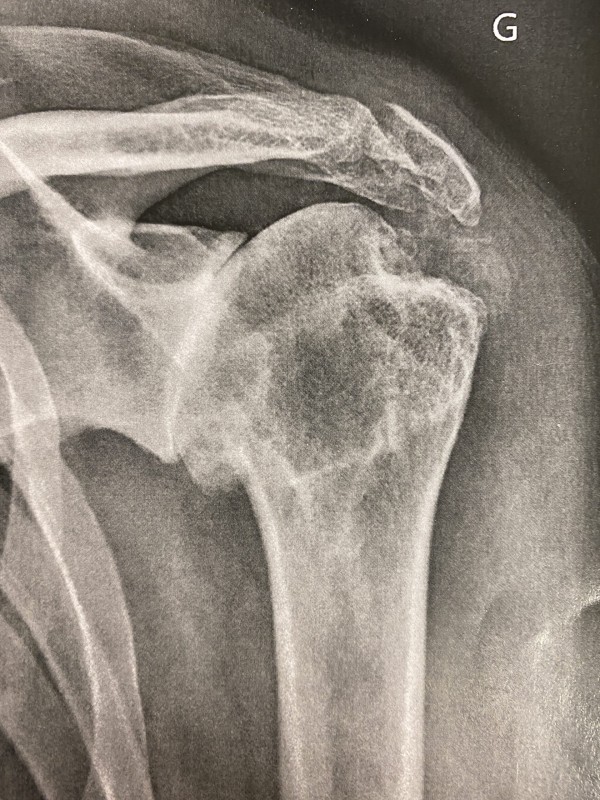

L'ARTHROSE EXCENTRÉE avec rupture de coiffe

• La zone malade arthrosique est généralisée à toutes les articulations entre la tête humérale et l’omoplate (zone rouge), elle est dite « excentrée » car la tête humérale n’est plus retenue et vient buter contre l’acromion de par l’absence plus ou moins importante des tendons de la coiffe des rotateurs.

• La fonction de l’épaule est très perturbée – Age moyen de survenue : > 70 ans.

l'arthrose (rouge) est généralisée à toutes les articulations de l'épaule

les tendons sont détruits en plus ou moins grand nombre